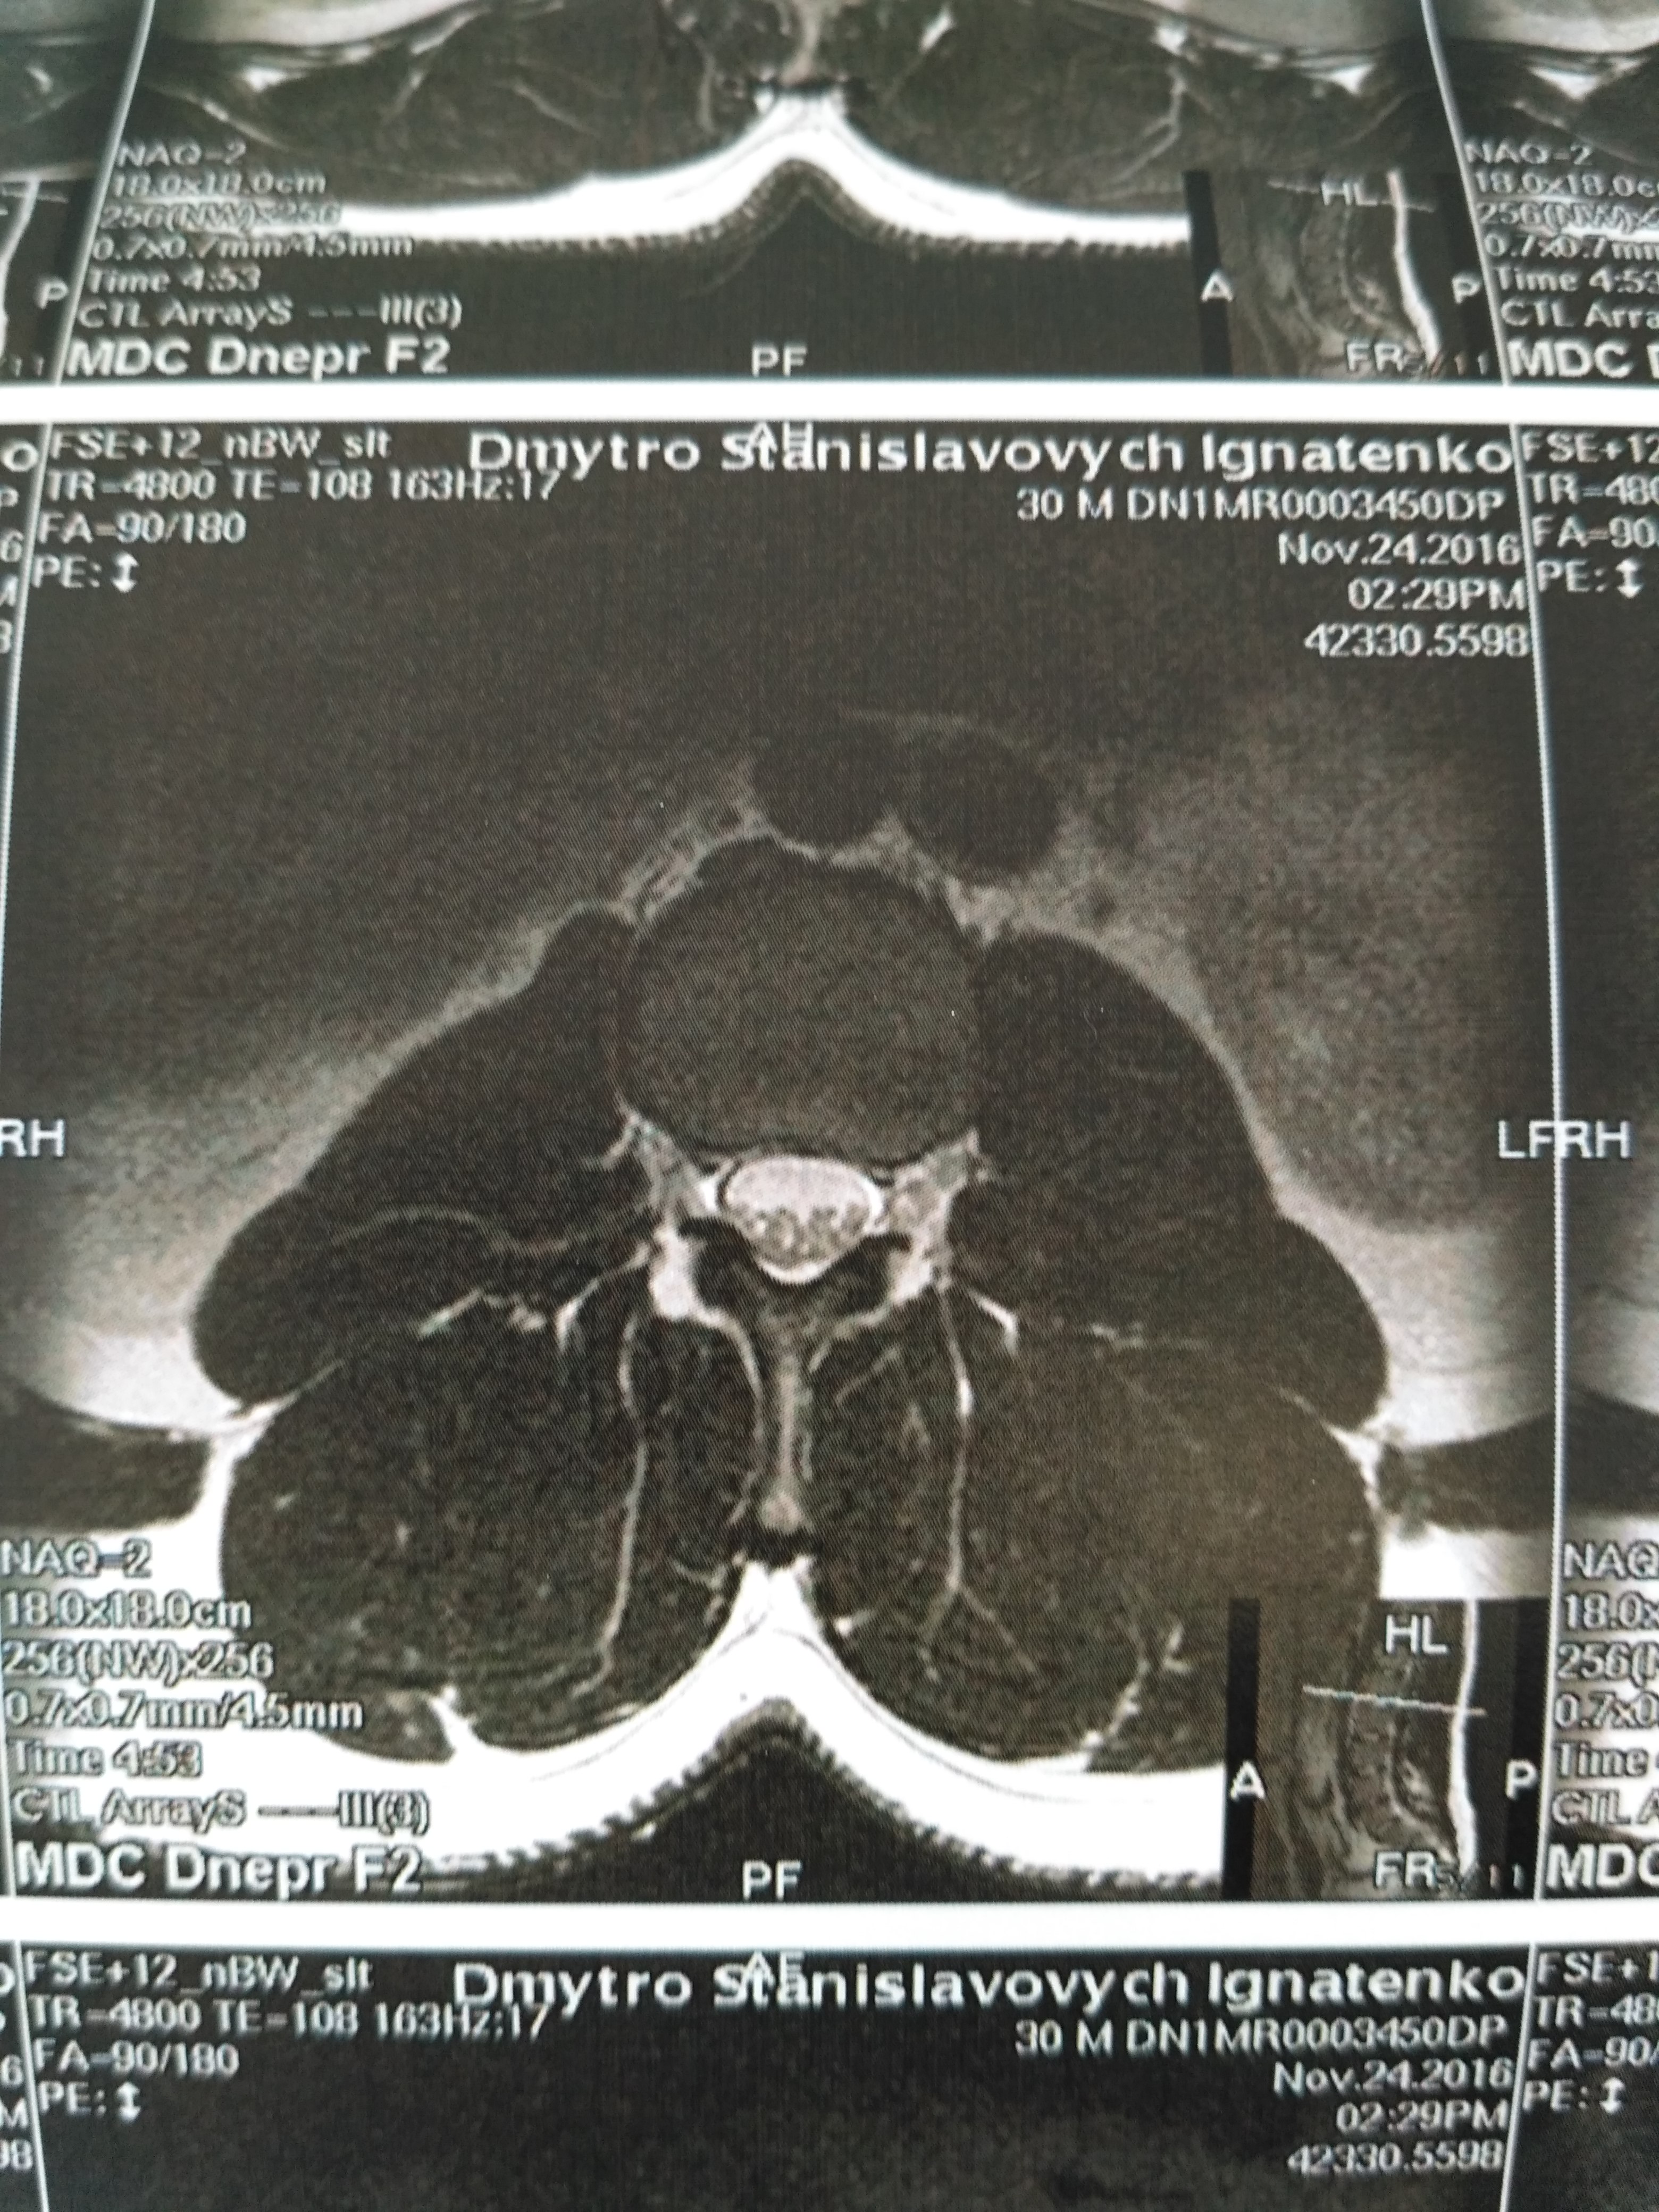

Тренировки с межпозвоночной грыжей.